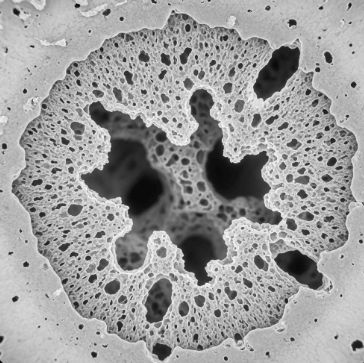

골밀도는 뼛 속에 칼슘과 미네랄이 얼마나 조밀하게 들어있는지를 나타내는 수치입니다.

뼈는 겉으로 보기엔 단단해 보이지만, 실제로는 끊임없이 생성과 분해를 반복하며 재생되고 있어요. 나이가 들면서 뼈를 만드는 속도보다 분해되는 속도가 빨라지면 골밀도가 낮아지게 됩니다.

골다공증은 뼈에 구멍이 많이 생긴 것처럼 뼈가 약해져서 작은 충격에도 쉽게 골절되는 질환입니다.

'침묵의 질병'이라 불릴 만큼 골절이 발생하기 전까지는 증상이 거의 없어요. 하지만 한 번 골절이 발생하면 회복이 어렵고, 연쇄 골절로 이어질 위험이 높습니다.